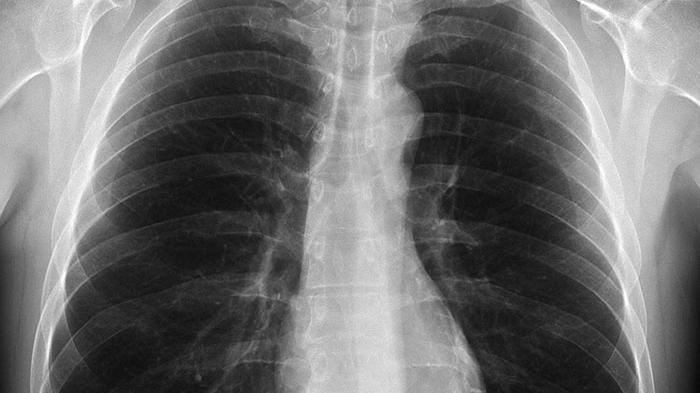

TRIBUN-BALI.COM, NEGARA - Sebanyak 200an kasus positif TBC (Tuberculosis) di Kabupaten Jembrana setiap tahun. Dari jumlah tersebut, 5 orang warga Jembrana TB-HIV saat ini.

Menurut data yang diperoleh dari Dinas Kesehatan Jembrana, dalam kurun waktu tiga tahun terakhir ini sudah ada sebanyak 618 orang mengidap penyakit yang disebabkan oleh bakteri Mycobacterium ini.

Rinciannya, pada tahun 2023 ada 2.915 orang terduga TBC dan tercatat 286 kasus positif. Pada tahun 2024 tercatat ada 2.867 orang suspek TBC dengan jumlah kasus positif sebanyak 223 orang. Sementara hingga pertengahan bulan Juni 2025 ini tercatat sudah ada 1.216 orang suspek dengan jumlah 109 kasus positif TBC yang ditemukan di Jembrana.

"Untuk penyakit TBC ini khusus atau berbeda dengan penyakit lainnya. Semakin banyak screening dan semakin banyak kasus, semakin bagus. Sehingga kita bisa melakukan penanganan yang lebih tepat dan menekan angka penularan," ungkap Kepala Bidang Pencegahan dan Pengendalian Penyakit (P2P), Dinas Kesehatan Jembrana, dr I Gede Ambara Putra saat dikonfirmasi.

Menurut data, kata dia, temuan kasus ini karena penerapan atau pelaksanaan screening yang optimal. Sasarannya adalah semua orang yang menunjukkan gejala serta lakukan skrining terhadap kelompok berisiko. Seperti kelompok ODHA, mereka yang tinggal di lingkungan kumuh serta lingkungan dengan padat penduduk.

“Saat ini bahkan ada sebanyak 5 orang yang mengidap TB-HIV. Mereka menderita dua penyakit sekaligus sehingga dapat pengawasan yang khusus untuk memastikan pengobatannya berjalan dengan baik,” jelasnya.

Ambara mengatakan, pencegahan meluasnya penyakit menular ini melalui deteksi awal gejala TBC perlu digencarkan lagi. Sebab, penularannya sangat mudah yakni melalui droplet (percikan air liur). Sehingga, upaya pencegahan dengan deteksi dini gejala awal harus terus ditingkatkan setiap tahunnya.

"Untuk deteksi dini, kita sudah memiliki kader-kader mitra kesehatan yakni kader perempuan PKK tersebar di desa yang tugasnya sangat potensial untuk menyebarluaskan ini. TBC bisa sembuh 99 persen, asal pengobatan berjalan baik, tidak disertai penyakit lain, dan asupan gizi yang baik," tandasnya.